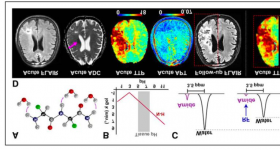

血管功能對癡呆和阿爾茲海默癥的作用逐漸被人們重視。最近研究表明,血腦屏障(blood–brain barrier, BBB)破壞...